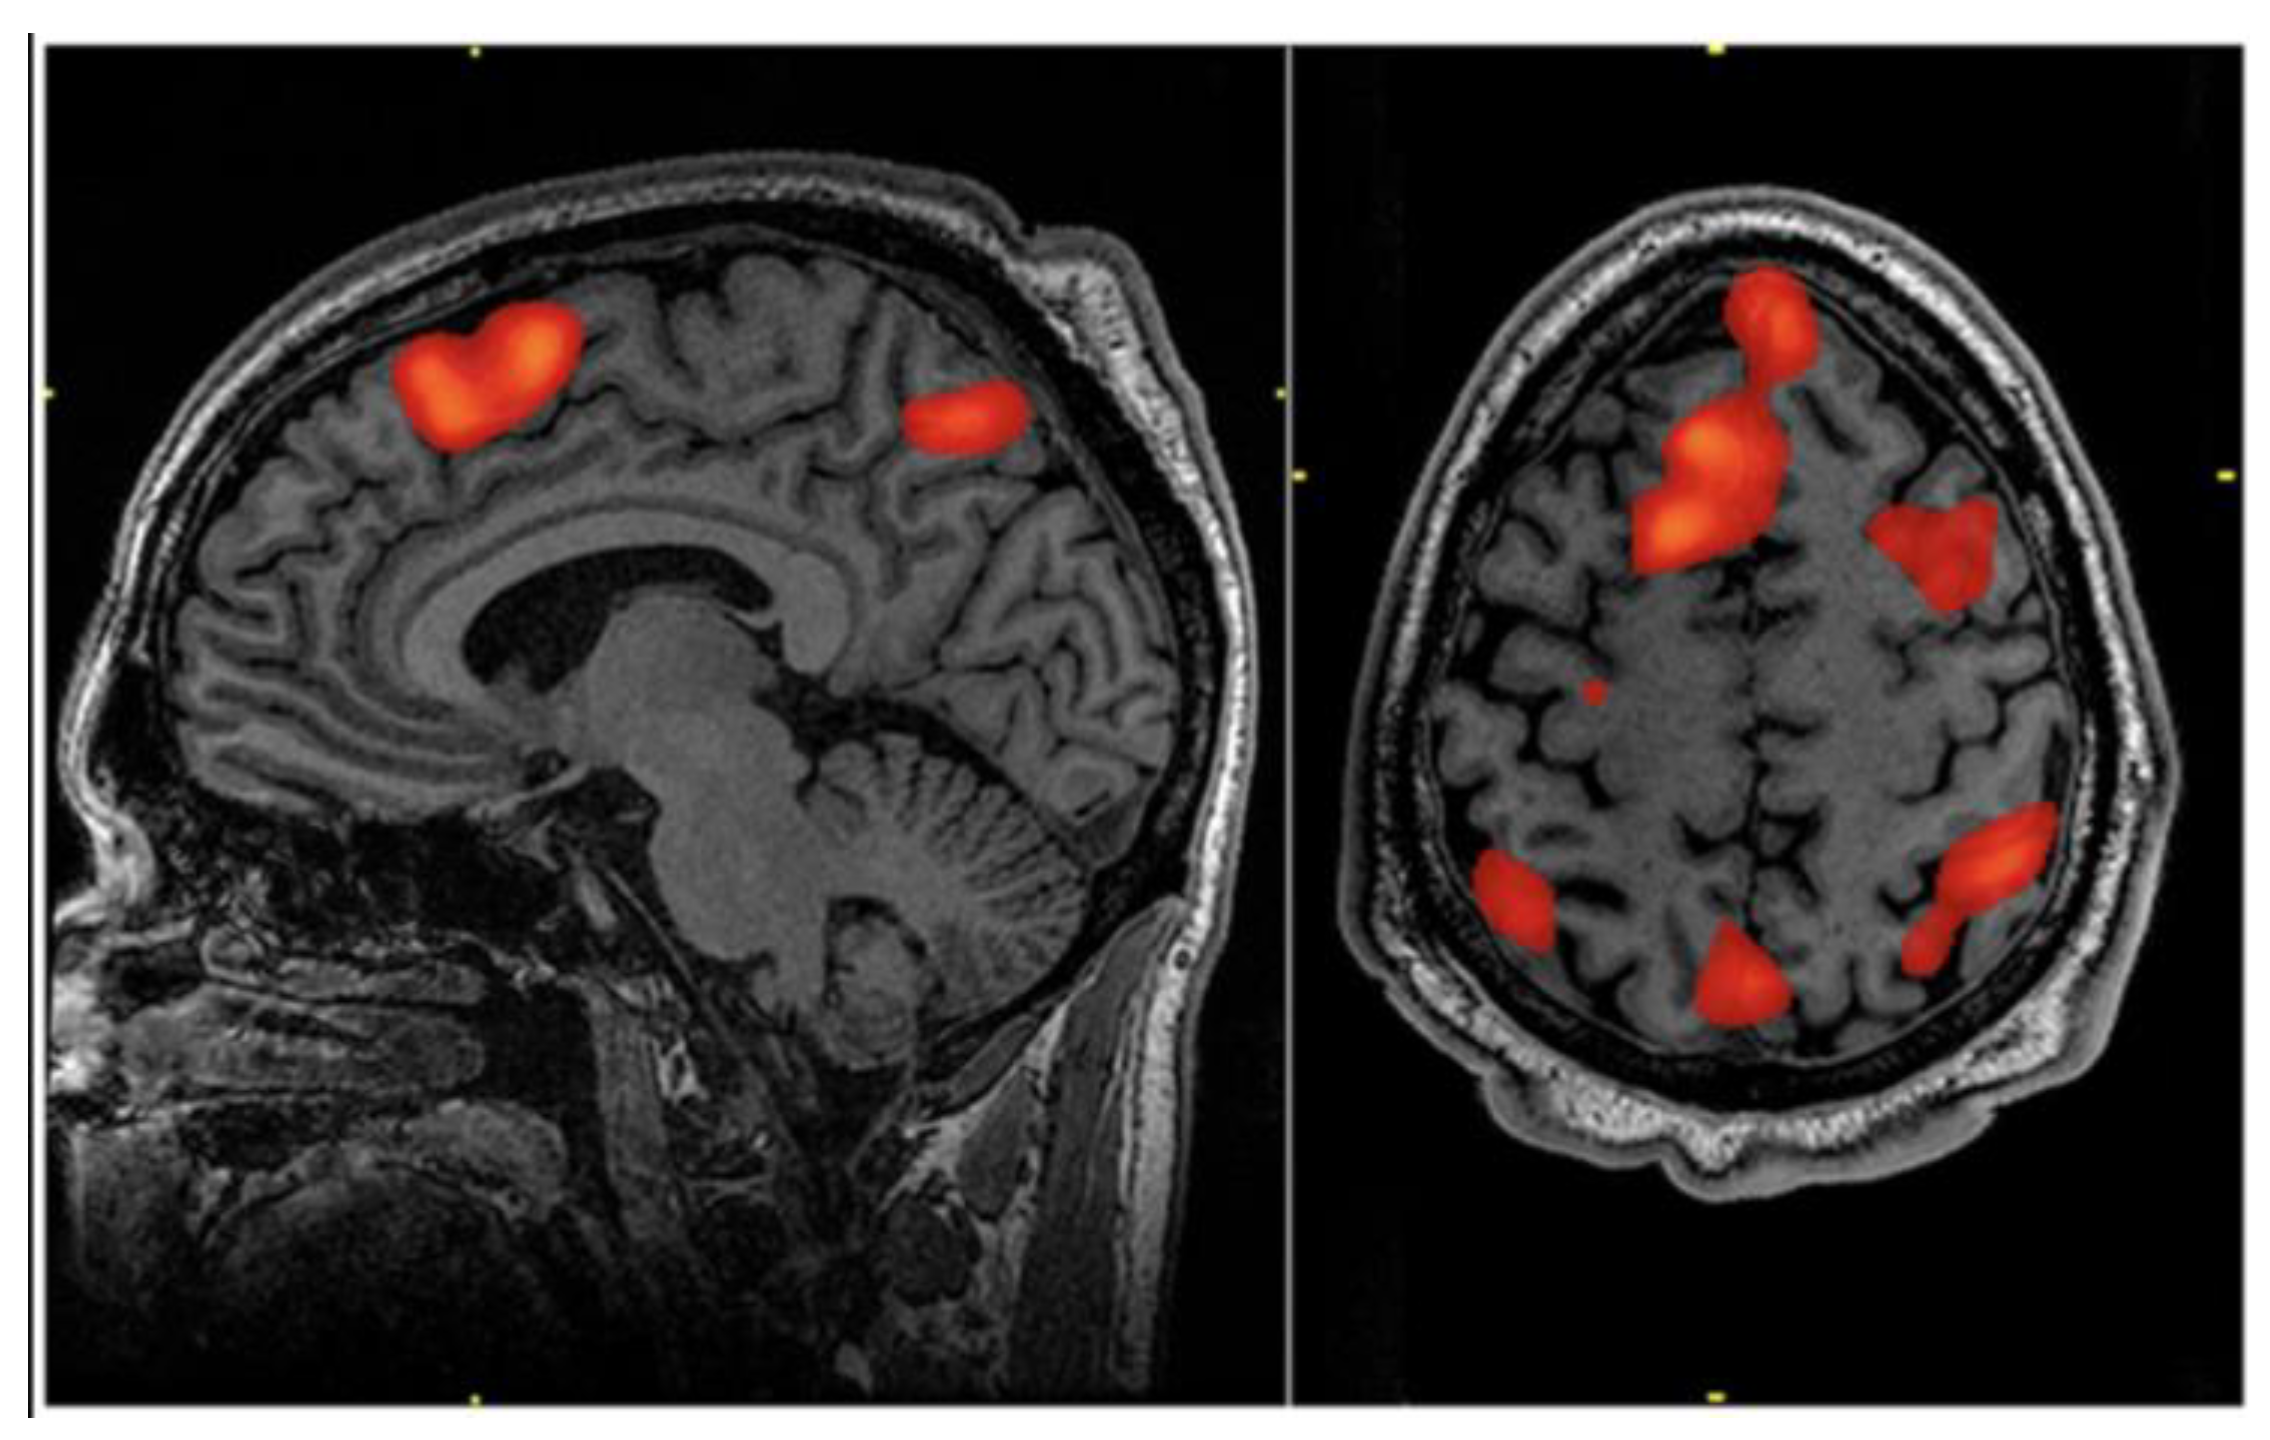

Functional magnetic resonance imaging (fMRI) has long been a cornerstone of brain research, but its application to the spinal cord presents unique and significant technical challenges (Table 1) (Figure 4) [64]. The spinal cord's small cross-section, its proximity to the vertebral column, and the physiological noise from surrounding organs, such as the lungs, introduce strong spatial inhomogeneity and temporal fluctuations in the magnetic field [9,64]. Despite these hurdles, remarkable progress has been made, particularly with the advent of ultra-high field systems.

An important advancement in spinal cord imaging is 7 Tesla (7T) axis-resolved fMRI [1]. In order to resolve fine-grained functional organization within the spinal cord, including laminar-specific mapping, this higher field strength allows for improved sensitivity to the blood oxygenation level-dependent (BOLD) signal and superior spatial resolution [9]. Using both single-shot and multi-shot 2D echo-planar imaging (EPI) protocols, early research has effectively shown that group-level sensory task fMRI in the cervical spinal cord at 7T is feasible [9]. Depending on the needs of the experiment, multi-shot EPI (0.60 mm) offers a trade-off between sensitivity and spatial precision, while single-shot EPI (0.75 mm in-plane resolution) typically produces the highest mean z-statistic. Multi-shot EPI also offers better-localized activation clusters and less geometric distortion [9].

The drive towards ultra-high field fMRI for spinal cord imaging reflects a critical need for higher spatial and laminar resolution. This advancement is vital for moving beyond macro-level observations to a detailed, circuit-level understanding of spinal function in vivo. The ability to map activity across Rexed laminae, defined by their cellular structure and function, is crucial for unraveling the complex processing of sensory and motor information within the spinal gray matter [10,11,12,13,14,15].

Figure 4. An fMRI scan performed during working memory tasks typically demonstrates activation in the bilateral superior frontal cortex and the superior regions of the bilateral parietal cortex. This work is in the public domain in the United States because it is a work prepared by an officer or employee of the United States Government as part of that person’s official duties under the terms of Title 17, Chapter 1, Section 105 of the US Code with permission from Wikimedia Commons [64].